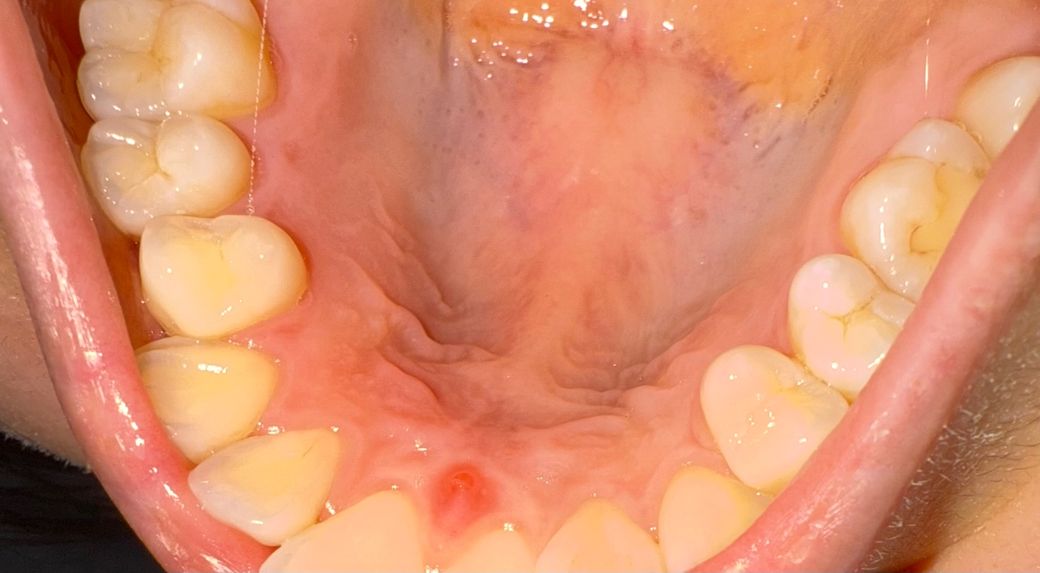

앞니 입천장이 부었는데 신경문제 일까요ㅠ??1

저렇게 뾰루지가 났는데 어제 뜨거운걸 먹긴 했어요 이빨은 통증 아예 없는데 곧생리라 컨디션이 많이 안좋긴 해요 저거 고름주머니 일까요??ㅠ

그냥 단순 상처로 때문에 생긴 염증으로 보입니다. 치아뿌리 끝에서 생긴 염증이라면 조금 더 아래쪽이어야 하며, 잇몸에서 생긴 염증이라면 더 윗쪽이어야 합니다. 그냥두면 며칠 지나면 없어질 것으로 보입니다.

사진에 보이는 곳은 앞니부위신경이 지가는곳으로 약간 튀어 나와 있습니다. 신경 문제는 아니고 저 부위가 자극을 받아서 생긴 현상입니다. 시간이 지나면 괜찮아 지실꺼에요.

위 사진만으로는 명확히 알 수는 없으나 신경문제 보다는 잇몸에 상처가 생긴 것으로 보입니다.

사진으로 봤을 경우 잇몸이 자극이 되어 부은것으로 보입니다. 너무 딱딱한 음식을 먹다 손상이 된것일수 있습니다. 해당부위를 자극하지 않는다면 대부분 1주일정도 지나면 아물게 됩니다.

자세한 확인을 위해서 치과에서 진료를 받아보는 것을 권유드립니다.

해당 부위 국소적으로 염증이 있을때 나타날 수 있는 증상같습니다 잇몸치료 받아보시기 바랍니다